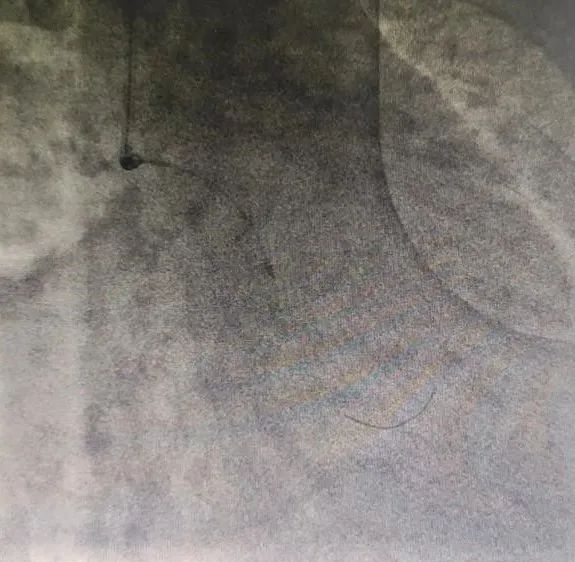

激光导管进行销蚀治疗

患者是一位84岁的老年女性,诊断为急性前壁心肌梗死,就诊时间已超过48小时,错过最佳再灌注时机,并且出现了心力衰竭并发症。医生予以充分优化的药物治疗后,病情逐步稳定,在患者心梗第7天予患者实施了冠脉造影检查,术中显示前降支为梗死相关动脉,左主干及前降支近端严重狭窄(99%)伴重度的钙化,导丝艰难通过后,应用常规介入方法球囊不能通过,刘巍主任团队遂采用准分子激光冠脉销蚀技术,成功开通梗死相关血管,并在前降支-左主干植入支架,患者恢复良好,无介入相关并发症发生。